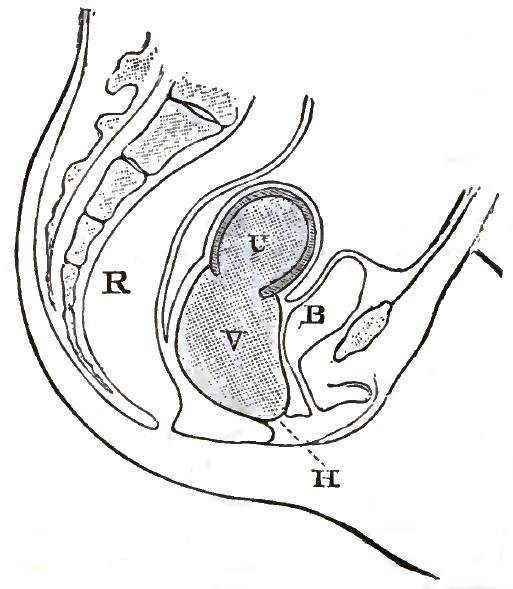

| 2. | THE CORRECT REPRESENTATION OF THE PELVIC ORGANS |

| 3. | FIRST DEGREE OF PROLAPSE OF THE POST-PARTUM UTERUS |